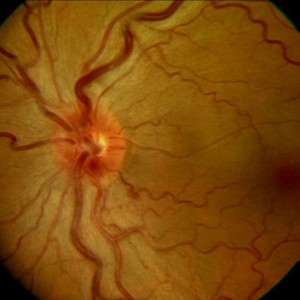

hyperämische Papille

Papillenhyperämie